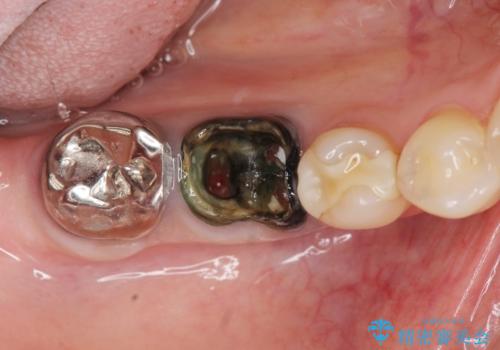

脱離した歯を精査したところ、大きな虫歯の再発・穿孔箇所が複数認められ長期的な予後を見込むことが難しかったため抜去が妥当であると診断しました。

抜歯後は、奥の銀歯も一緒に白くできるブリッジ治療を希望されました。

(※今回のケースではインプラントも治療の選択肢として可能でした。)